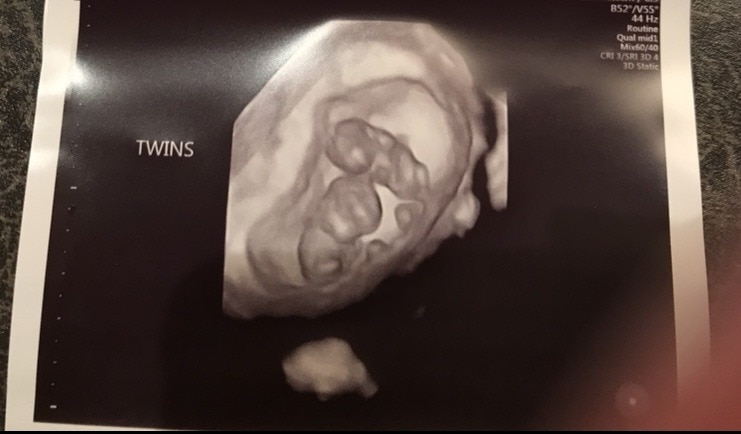

Ultrasound Photos of 9 Weeks Pregnant With Twins